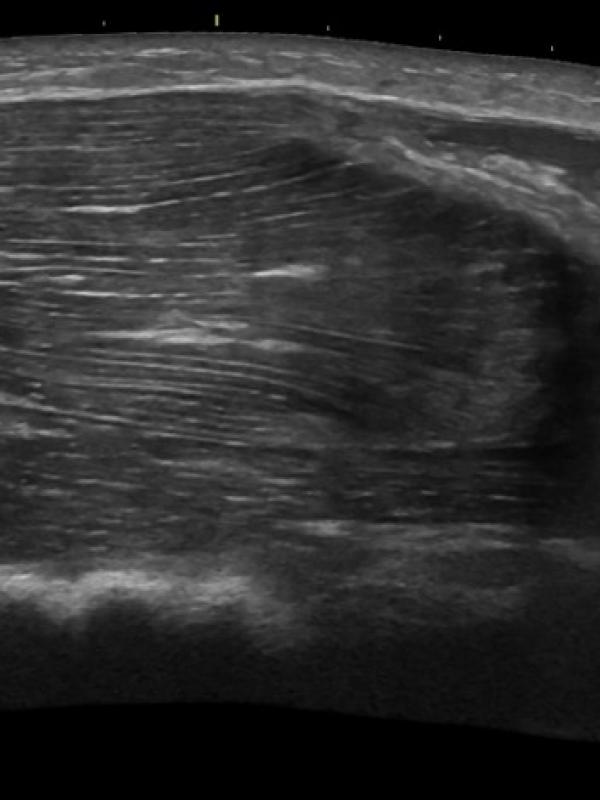

Musculoskeletal ultrasound

Musculoskeletal ultrasound (MSK)

Ultrasound imaging of tendons, ligaments, and muscle groups. Referring providers order musculoskeletal ultrasound for a number of reasons. Some common reasons are: suspicion of muscle or ligament/tendon tear or damage, trigger finger or lump.

Musculoskeletal ultrasound FAQ

• What is the preparation needed for my MSK ultrasound? No preparation is necessary.

• Who interprets the MSK ultrasound? Sound Health Imaging contracts with Proscan reading services and Specialist Direct reading services. They are fellowship-trained, board certified radiologist with subspecialty training.

• When and how will I get results? The MSK ultrasound exam will be read by the radiologist within 24 hours of your study (unless the study indicates need for results sooner). Final results will be sent directly to your referring provider the week-day after your exam.